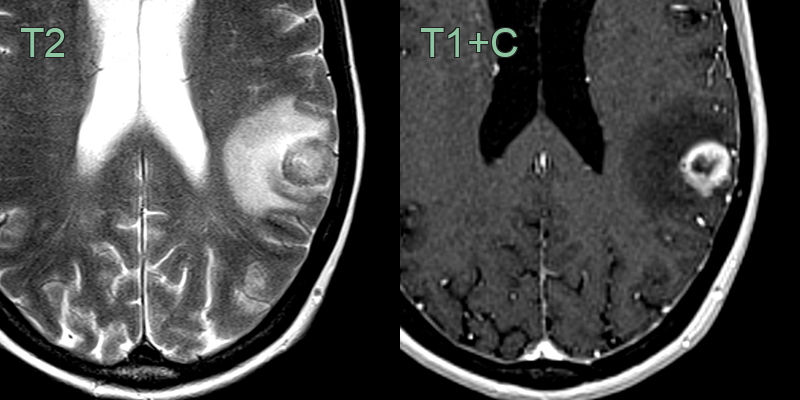

- A 60-year-old patient who was diagnosed with colonic cancer three years prior presented with a right visual field defect and headache.

- A large left occipital lobe lesion showed peripheral enhancement and was surrounded by vasogenic edema.

- The peripheral T2-hypointensity within the lesion has been reported to be related to collagen accumulation.